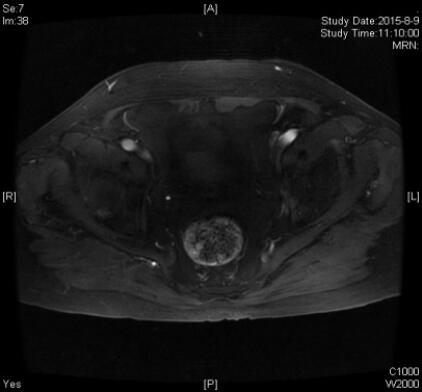

盆腔增强MRI检查,典型图片如下:

刘晓航教授:首先我们先看第三张图像,这是原发灶的图像,可见前列腺体积增大,两侧外周带,右侧的中央带和移行带广泛强化,符合前列腺癌的改变。另外,右侧中央带和移行带的肿块比较大,已经明显越过中线,对尿道形成了挤压,因此患者有比较明显的尿路梗阻的症状。同时前列腺的包膜也不太光整,肿瘤可能已经累及,但未侵犯周围的盆壁和直肠。然后我们再回来看前两张图像,可以看见两侧髂血管旁多发肿大淋巴结,短径至少2 cm,增强后可见明显强化,但没有明确的坏死,符合转移淋巴结表现。根据上述表现,可以诊断为:前列腺癌伴双侧髂血管旁多发肿大淋巴结;转移可能。